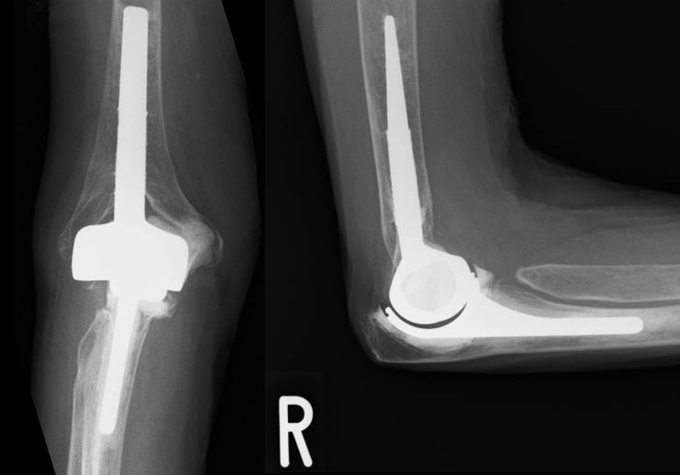

上腕骨遠位端骨折

肘を構成する上腕骨の末端が折れる外傷で、転倒や交通事故などで強い衝撃が加わって発生します。関節面のずれや骨片の転位を伴うと、肘の安定性と可動域が大きく損なわれます。治療の基本は、プレートやスクリューによる解剖学的整復と強固な固定であり、手術後は早期からリハビリを開始して肘の動きを保つことが極めて重要です。高齢者では骨の脆弱性や全身状態に応じて、保存加療や人工関節置換術を選択することもあります。

症例 50代 女性

(術前)

(術後 12か月)